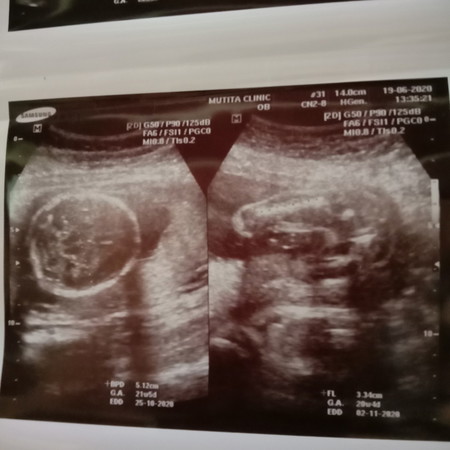

ดูตรงไหนค่ะว่าเพศอะไร

น่าจะผู้หญิงนะคะแม่

ลึ้นดูค่ะ